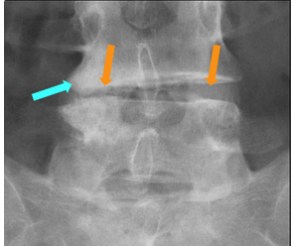

Q

What is shown on this X-ray?

A

Asymmetry in osteoarthritis